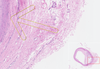

Atherosclerosis of the Artery

Adventitia

Atheroma

Clefts after washing up Cholesterol Crystals

Granular Deposits of Calcium

Intima

Lipophages

Lumen and Fibrous Cap

Lymphocytes

Media

Necrotic Detritus

New Blood Vessels